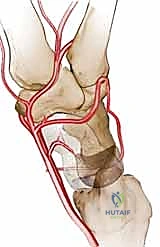

التروية الدموية: نقطة الضعف القاتلة

السبب الجذري لمرض كينبوك يكمن في التروية الدموية الفريدة (والهشة أحياناً) للعظم الهلالي. تتلقى معظم العظام الدم من عدة أوعية دموية تدخل من اتجاهات مختلفة. ومع ذلك، في حوالي 20% إلى 30% من البشر، يتلقى العظم الهلالي إمداده الدموي من وعاء دموي واحد فقط (Single Volar or Dorsal Artery). إذا تعرض هذا الوعاء الدموي الوحيد للانسداد، أو التمزق بسبب صدمة، أو الضغط المستمر، فإن العظم يُحرم من الأكسجين والمواد المغذية، مما يؤدي إلى بداية عملية النخر (موت الخلايا العظمية).

2. يتم تحديد قطعة صغيرة من العظم السليم من منطقة قريبة (غالباً من عظمة الكعبرة السفلية - Distal Radius).

3. الجزء الحاسم: لا يتم أخذ العظم فحسب، بل يتم استئصاله مع الشريان والوريد المتصلين به (Pedicled graft). هذا يعني أن قطعة العظم المنقولة لا تزال حية وتنبض بالدم.

العظم الكبير (Capitate) هو أكبر عظام الرسغ ويقع مباشرة فوق العظم الهلالي. القوة المركزية لليد تنتقل من العظم الثالث في المشط، إلى العظم الكبير، ثم تصطدم مباشرة بالعظم الهلالي.